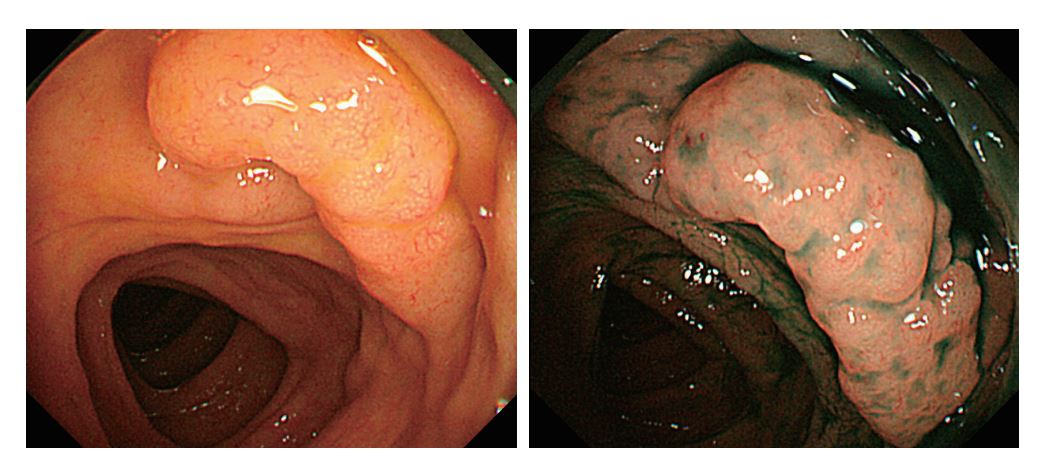

過形成ポリープと誤診された直腸の「十二指腸型濾胞性リンパ腫」

こちらのサイトより引用させていただきました

「十二指腸型濾胞性リンパ腫」というのは、最近、確立された疾患概念で独特の染色体異常で診断される。MALTリンパ腫と同じく、予後は良好であり「経過観察で十分」という意見が多い(資料)。

本症例でも直腸ポリープのポリペクトミー後「経過観察」とされたが、4か月後に胃と十二指腸に同じ病変が出現したために化学療法が施行された。